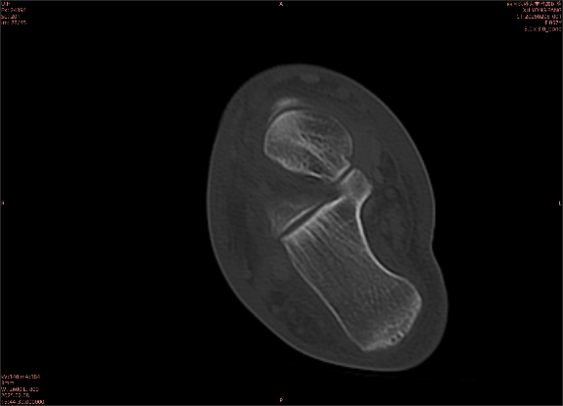

舉例圖像

圖2

專業(yè)解釋看不懂沒關(guān)系,大家看圖1和圖2就可以了,這是同一個患者跟骨的磁共振和CT圖像,圖1的紅色箭頭指示的黑線就是磁共振圖像顯示的骨折線,一目了然。而對比圖2的CT圖像上并未顯示異常。